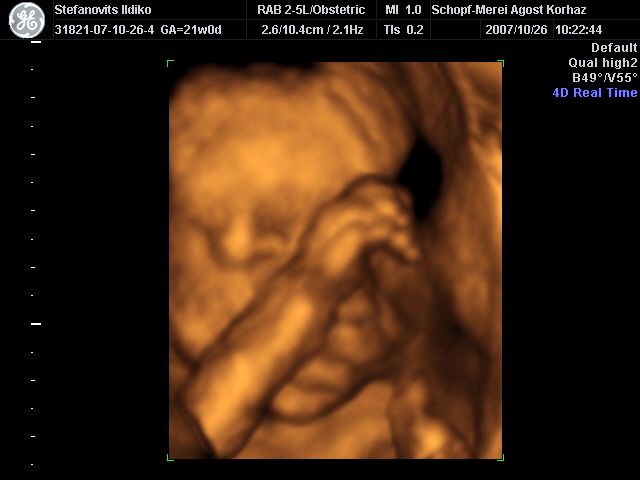

4D Ultrahang - 21+1 (07/10/26, Bp.)

4D - 3